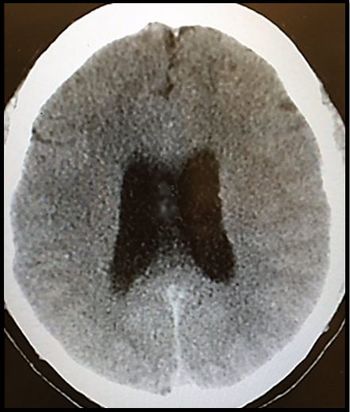

A 34-year-old man with a history of HIV says family members are exaggerating his symptoms but that the headache and double vision are bothersome.

Here’s a case in point about progressive multifocal leukoencephalopathy in a patient with long-standing HIV who had never taken HART.